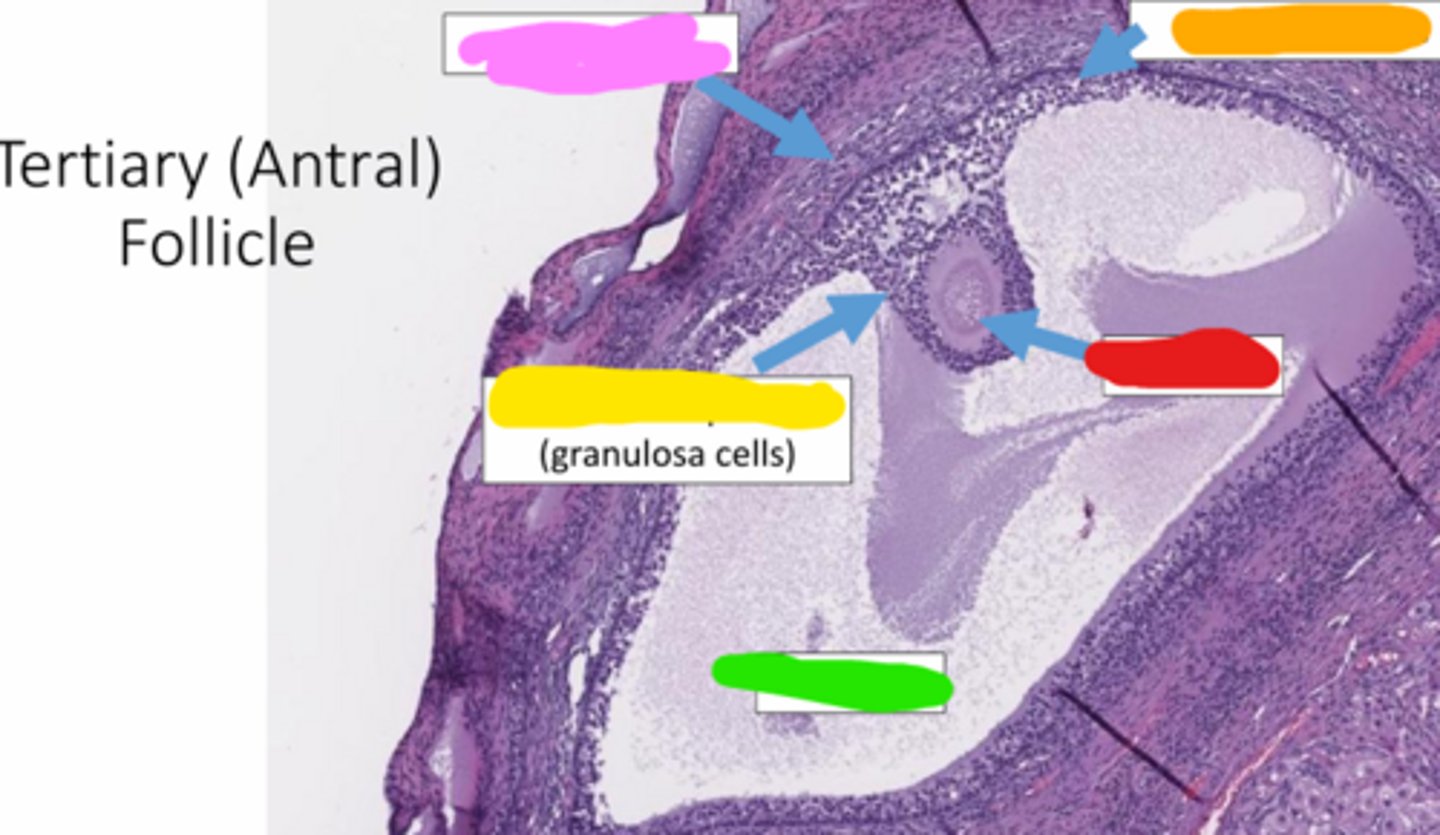

tertiary

this is a _____ follicle

antrum

the fluid filled space, marked by the X, is called the _____

cumulus

the yellow cells surrounding the oocyte in the antral follicle are called ____ cells

theca cells

yellow

green

granulosa cells

pink

orange

oocyte

red

cumulus oophorus

a mound of granulosa cells that covers the oocyte and secures it to the follicle wall (yellow)